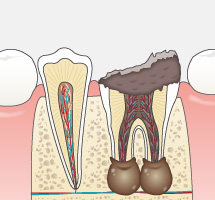

今まで一般的に行われていたむし歯治療は、痛くなったら歯医者に行き治療する、という流れの繰り返しではなかったでしょうか?痛くなってから、むし歯が進行してからの治療は削る・抜歯することが多くなり、徐々に自分自身の天然の歯は「詰め物」や「被せ物」さらには「インプラント」や「入れ歯」になっていきます。天然歯は削ってしまうと二度と元には戻りません。

可能な限りご自身の歯で食事を楽しんだり、話したりして健康な生活を送っていただきたい。だからこそ当院ではできるだけ歯を残す治療をおこないます。単なる対症療法の“削って詰める”ではなく、病原菌の除去をしてからMI(Minimal Intervention:できるかぎり削らず、削っても最小の範囲で)の考えのもと原因療法を施し、治療後はむし歯の再発や新たなむし歯の発生を予防することを目標としています。